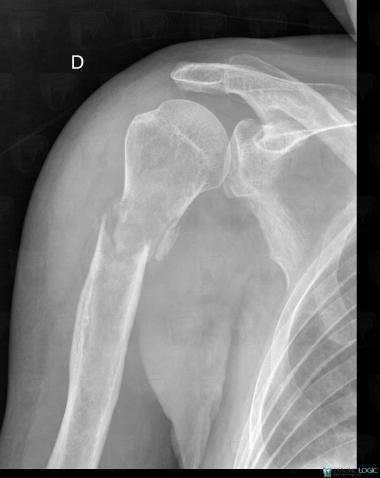

- Diagnosis Metastasis, Location(s) Humerus - Proximal part, with gamuts Ill-defined osteolysis, Meta-diaphyseal osteolysis

- Diagnosis Fracture, Location(s) Humerus - Proximal part, with gamuts